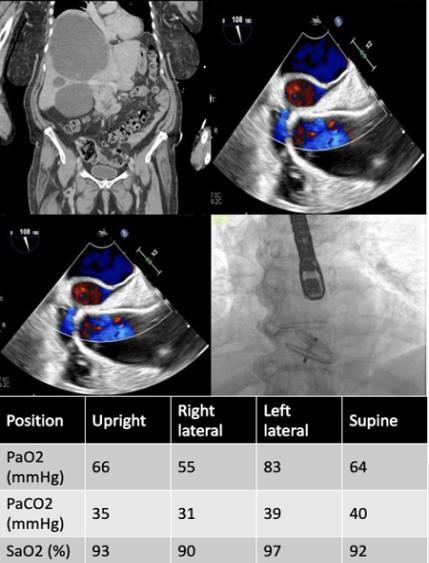

DELAYED DIAGNOSIS OF PULMONARY VEIN OCCLUSION AFTER ATRIAL FIBRILLATION ABLATION

Sara Luby1 , Jonathan M Oxman1 , Deepanjali Nair1, Alba Muñoz Estrella1 , Javier J Zulueta1